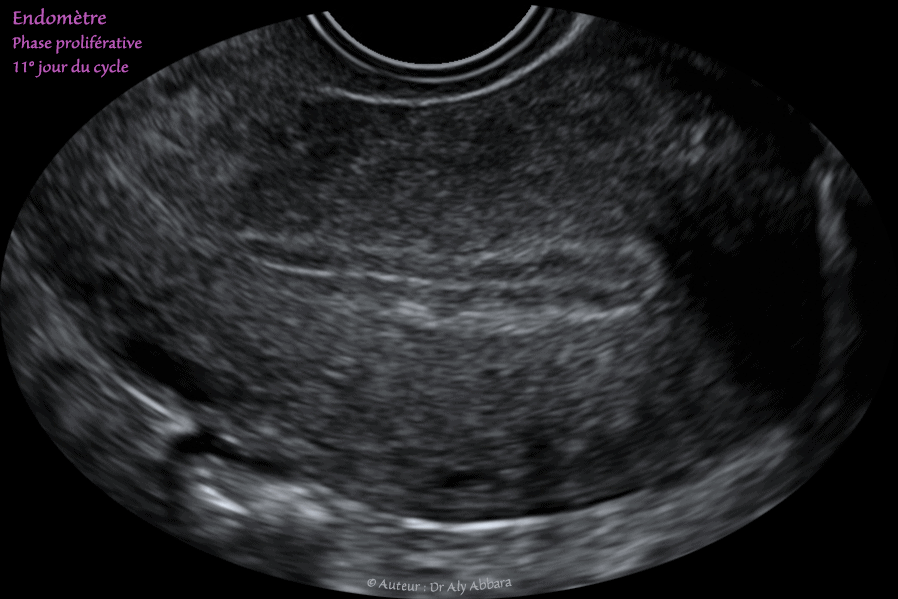

Utérus : l'aspect échographique habituel de l'endomètre de la phase proliférative (la phase estrogénique de la première moitié du cycle menstruel) :

Echographie réalisée au 11e jour du cycle menstruel - endomètre de 8 mm d'épaisseur.

Échographiquement, on observe entre le myomètre et la cavité utérine les couches successives suivantes :

• 1- Un très fin liseré anéchogène (discontinu sur l'image) correspondant à la zone de jonction entre le myomètre et la couche basale de l'endomètre.

• 2- La couche profonde de l'endomètre correspondant à la zone de renforcement basale (plus échogène que le reste de l'endomètre).

• 3- Les couches moyenne et superficielle de l'endomètre qui paraissent hypoéchogènes comparées à la couche basale profonde.

• 4- La ligne de la vacuité utérine qui prend l'aspect d'un liseré axial hyper-échogène.

Les trois dernières éléments donnent à l'endomètre de la phase proliférative son aspect échographique en trois feuillets.